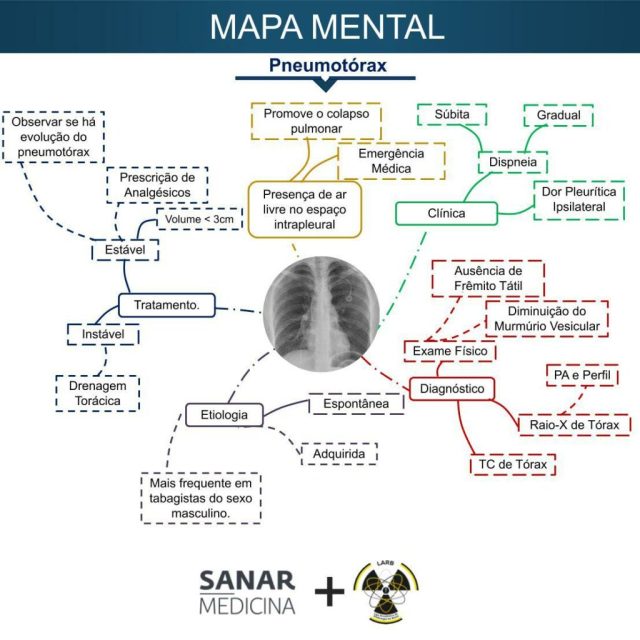

Pneumotorax o que é: uma condição pulmonar grave que muitos confundem com crise de ansiedade, mas que exige atenção médica imediata.

Pneumotórax explicado: como o ar invade o espaço pleural e causa colapso pulmonar

Em Destaque 2026: O pneumotórax é a presença de ar no espaço pleural, entre o pulmão e a parede torácica, que pode causar o colapso pulmonar.

Tipos de Pneumotórax: Classificação e Características Principais

Para entender melhor, os médicos classificam o pneumotórax em algumas categorias principais. A primeira é o pneumotórax espontâneo primário, que, como falamos, afeta indivíduos sem histórico de doença pulmonar, geralmente jovens, altos e magros. Acredita-se que pequenas bolhas de ar (bolhas subpleurais) possam se romper nesses casos.

Já o pneumotórax espontâneo secundário ocorre em quem já tem alguma doença pulmonar crônica. A fragilidade do tecido pulmonar aumenta o risco de vazamento de ar. Exemplos incluem enfisema, tuberculose ou câncer de pulmão.

O pneumotórax traumático, como o nome sugere, vem de um trauma. Pode ser fechado (sem ferida externa visível) ou aberto (com comunicação com o exterior). E o tipo mais perigoso: o pneumotórax hipertensivo. Aqui, o ar entra no espaço pleural, mas não consegue sair, criando uma pressão que comprime não só o pulmão, mas também o coração e os grandes vasos. É uma emergência médica gravíssima que pode levar à morte rapidamente.

Tratamento para Pneumotórax: Opções para Recuperar o Pulmão

O tratamento para o pneumotórax varia bastante, dependendo da gravidade. Em casos muito leves, onde o colapso é mínimo e o paciente está estável, o médico pode optar apenas por observação e repouso. O ar pode ser reabsorvido pelo corpo naturalmente.

No entanto, na maioria das vezes, é necessário drenar o ar acumulado. Isso é feito através de um procedimento chamado drenagem torácica. Um tubo fino é inserido no espaço pleural para remover o ar e permitir que o pulmão volte a se expandir. Este tubo geralmente fica conectado a um sistema de selo d’água.

Para casos mais graves ou recorrentes, pode ser necessária uma cirurgia. Procedimentos como a videotoracoscopia (VATS) podem ser usados para reparar o local do vazamento ou até mesmo para realizar uma pleurodese, que é um processo para colar a pleura visceral à parietal, prevenindo futuras entradas de ar.